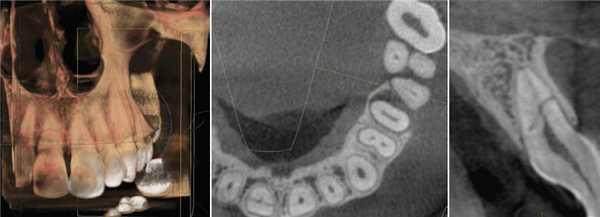

Ramamurthy и Matherene описывают ограниченность 2D изображений для определения MB2 каналов (Фото 1).

Фото 1: изображение MB2 в обоих первых молярах

Baratto Filho исследовали внутреннюю морфологию удаленных первых моляров верхней челюсти, сравнивая с данными, полученными при осмотре в микроскоп и при получении изображений КЛКТ ex vivo. Отчеты показали наличие 4-х каналов в 67,14% зубов и дополнительные корневые каналы в 92,85 % случаев в мезиобуккальном корне. Клиническая оценка показала слегка сниженный общий показатель (53,26%), но повышенный показатель выявления MB2 (95,63%), в то время как применение КЛКТ показало 37,05%. Ученые сделали вывод, что КЛКТ является хорошим методом для начальной оценки внутренней морфологии первого верхнего моляр, но для выявления устьев самым оптимальным способом является применение микроскопа. КЛКТ также применялся для выявления высокой встречаемости дистолингвального канала у Тайванцев, выявления аномалий в системе корневых каналов нижних премоляров, и помощи в выявлении искривлении корня (Фото 2).

Фото 2: Аксиальное изображение каналов C-формы во вторых молярах

С изобретением нового программного обеспечения для КЛКТ Orthophps CG3D/Galelios (Sirona, Germany) рабочая длина каналов также стала осуществляема. Но точность этих данных в клинической работе еще должна быть подтверждена (Фото 3).

Фото 3: Инструмент для измерения длинны корневого канала